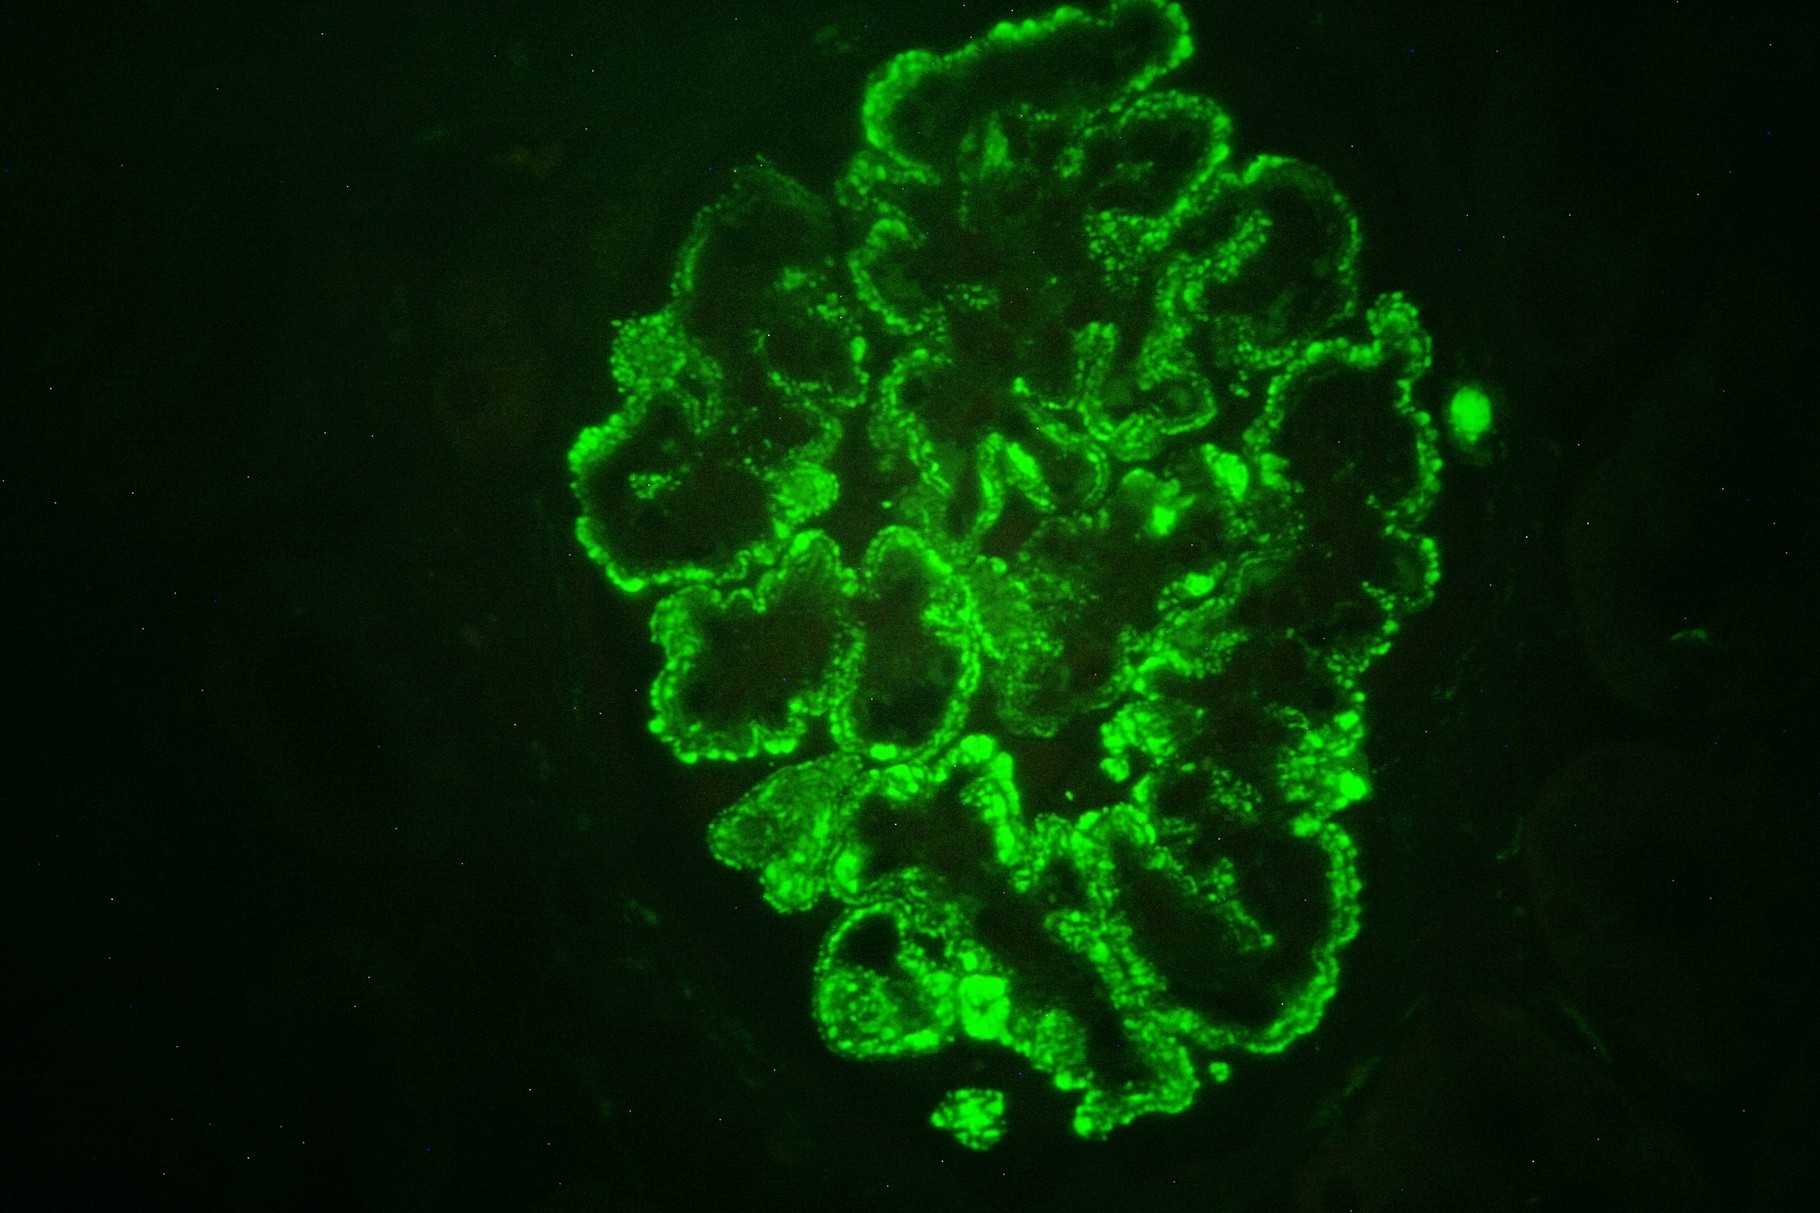

Patología Molecular

El diagnóstico sobre muestras de tejidos y líquidos corporales en plena era de la medicina del futuro, está basado en la integración de técnicas y conocimientos diferentes.

Hoy más que nunca es importante integrar una buena historia clínica con un correcto estudio de imagen y una buena morfología que además puede estar apoyada con proceso especiales complementarios relacionados con la Inmunología, Biología Molecular y Citogenética, generando así un estudio integral conocido como Patología Molecular.